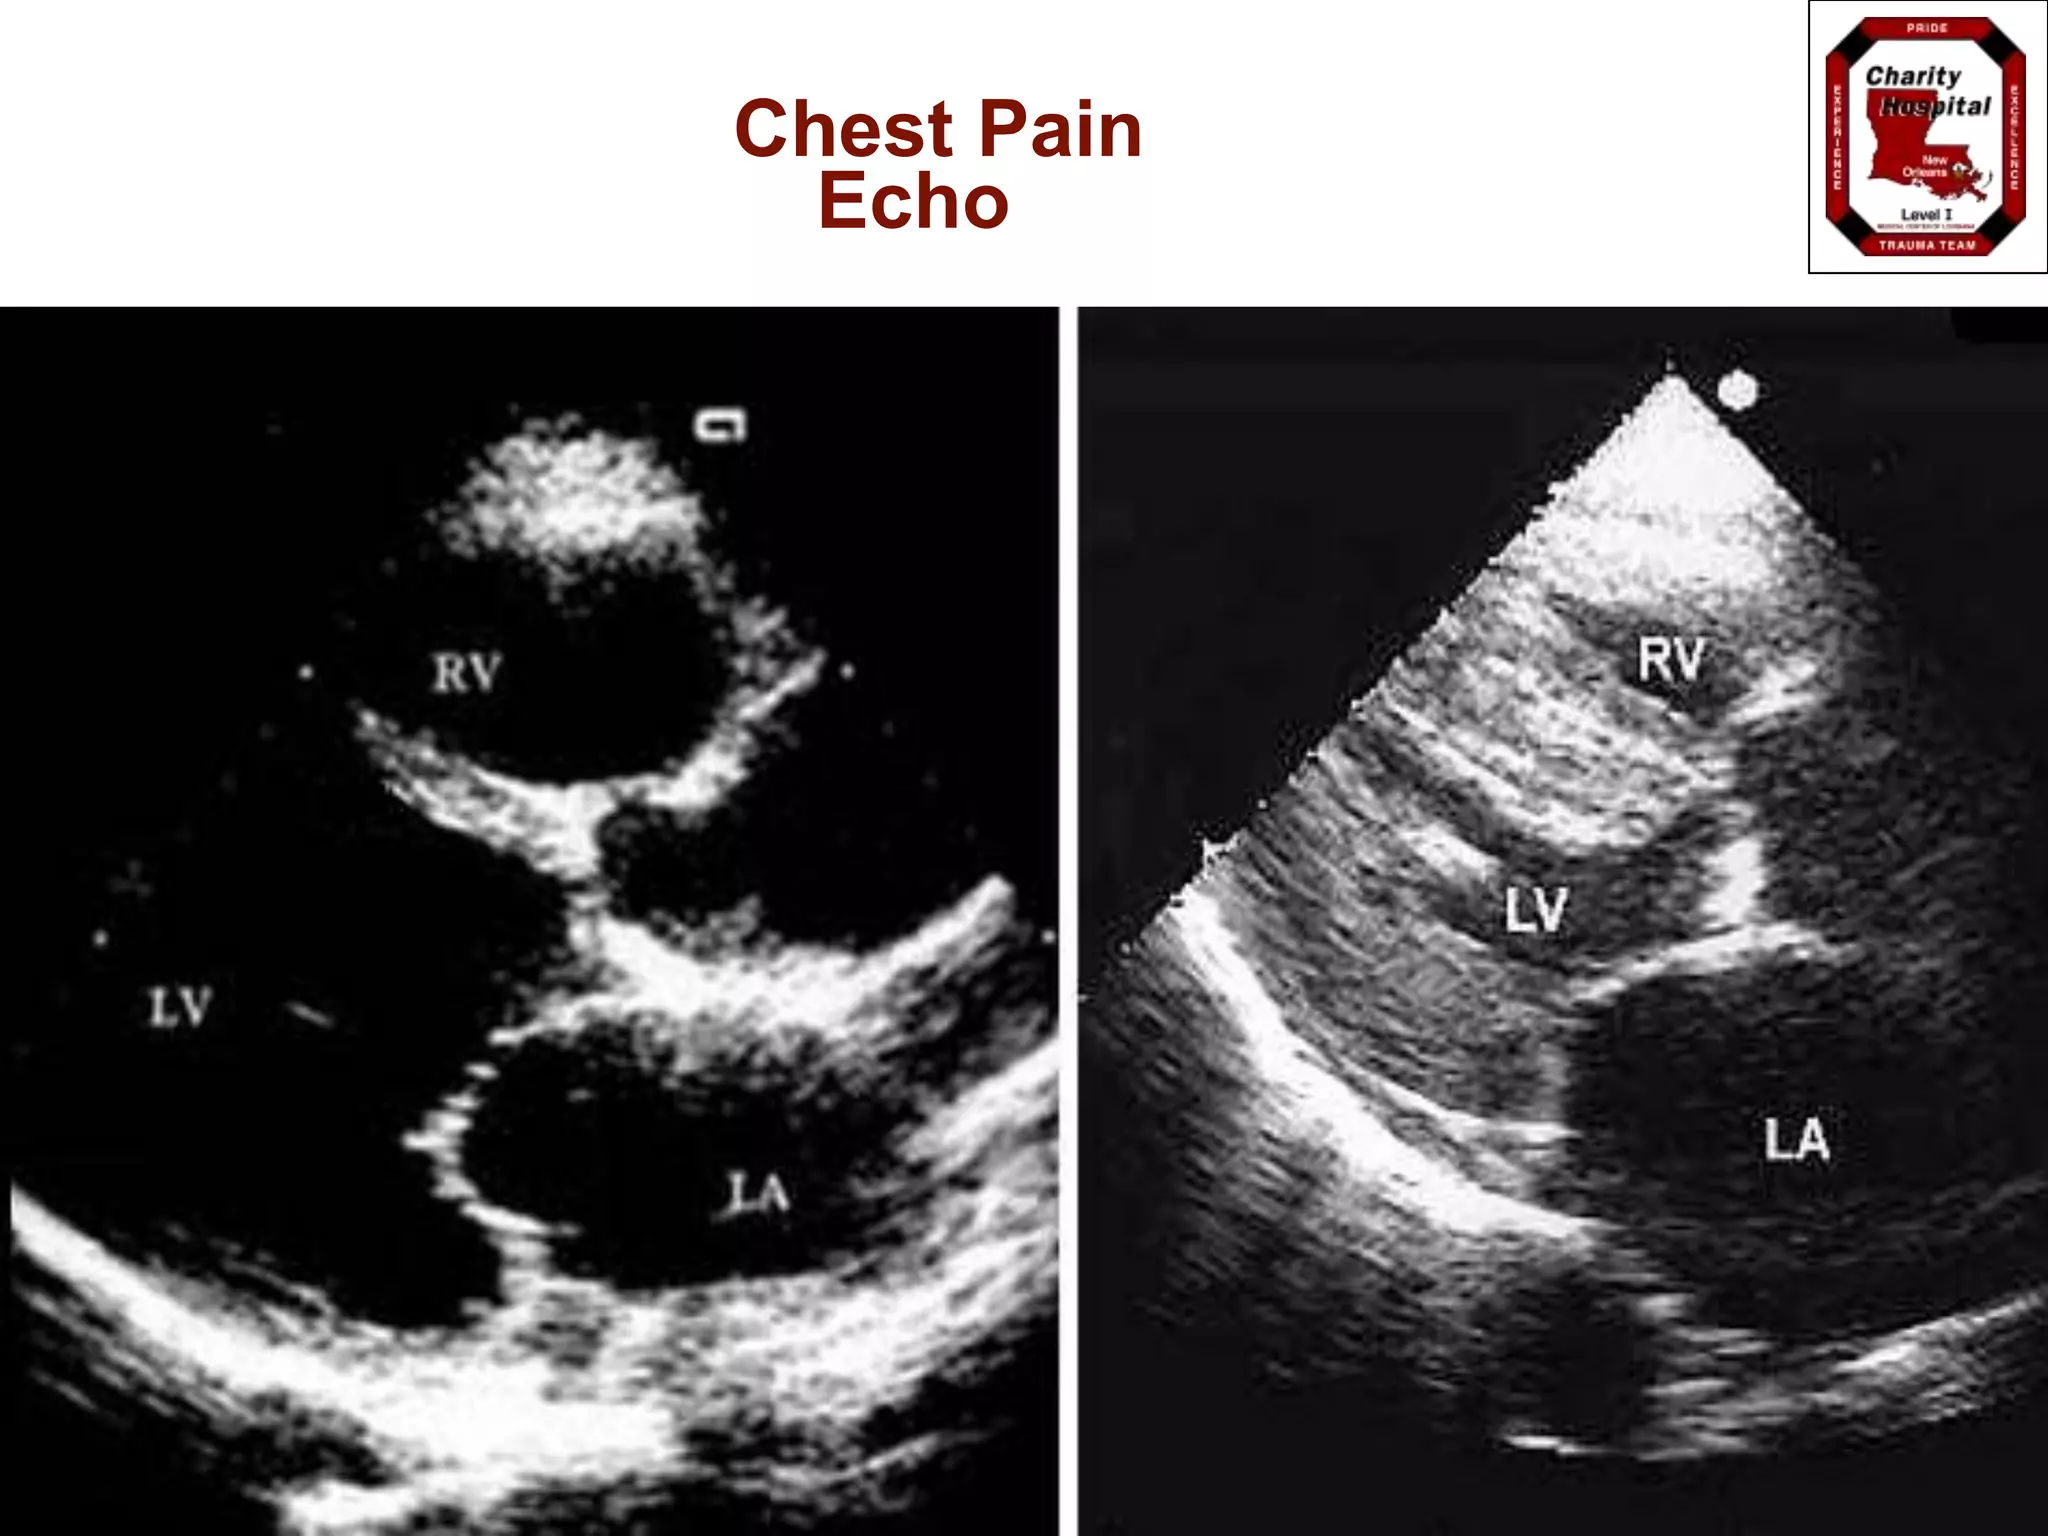

Echocardiogram

 Wall abnormalities occur within minutes

 Will detect abnormalities in 80% of AMI

 Normal resting echo in setting of chest pain

gives low probability

 Early screen for AMI complications:

aneurysms, valve abnormalities, other

structural destruction

Echo